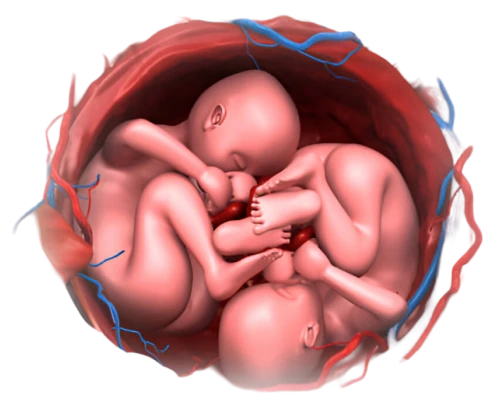

What is a Twin Pregnancy?

A twin pregnancy happens when a woman carries two babies in her womb at the same time. It can occur in two ways and both types of twin pregnancies require extra care and monitoring to ensure the best outcomes.

- 1. Identical Twins -: Formed when one fertilized egg splits into two.

- 2. Non-identical or Fraternal Twins -: Occur when two separate eggs are fertilized

Twin pregnancies occur in about 1 in every 80 pregnancies, but this rate may vary depending on factors like genetics, age, and fertility treatments.

Twin pregnancies come with higher risks compared to singleton pregnancies, including:

- Premature birth: Twins are more likely to be born prematurely (before 37 weeks).

- Low birth weight: Twins tend to have lower birth weights than singletons.

- Gestational diabetes: The risk of developing gestational diabetes increases in twin pregnancies.

- Preeclampsia: Women carrying twins are at higher risk of high blood pressure and preeclampsia.

- Placental issues: Placenta previa, placental abruption, or other complications can occur more frequently in twin pregnancies.

- Increased risk of cesarean delivery.

Some complications that can arise in twin pregnancies include:

- Twin-to-twin transfusion syndrome (TTTS): A condition where blood flow between the twins is uneven, affecting their growth and health.

- Intrauterine growth restriction (IUGR): When one or both babies don’t grow as expected.

- Preterm labor: As mentioned, twins are more likely to be born prematurely, which increases the risk of health problems.

- Gestational diabetes: Carrying twins increases the likelihood of developing gestational diabetes.

- Pre-eclampsia: A pregnancy complication involving high blood pressure and organ damage, more common in twin pregnancies.